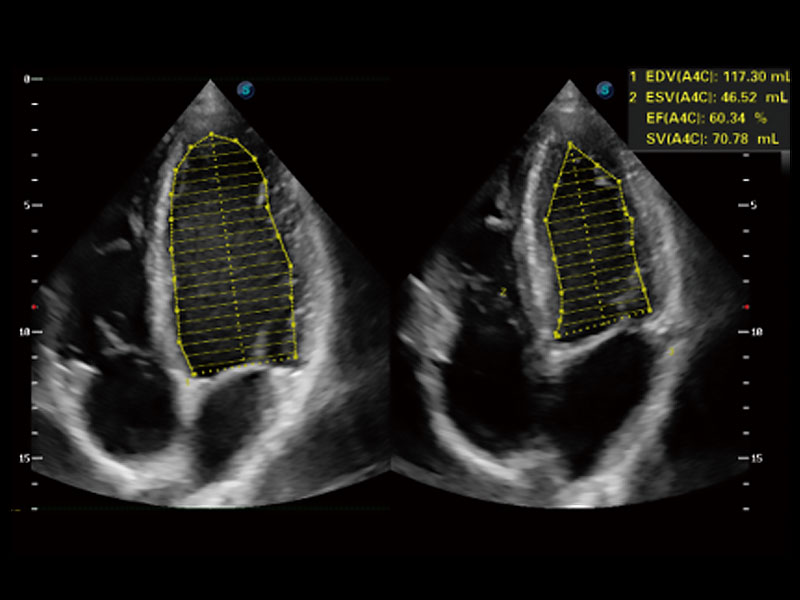

能夠基于左心室壁追蹤和辛普森法,自動(dòng)計(jì)算射血分?jǐn)?shù),支持多個(gè)可移動(dòng)點(diǎn)描跡,與手動(dòng)測(cè)量相比,極大節(jié)省了動(dòng)物醫(yī)生的時(shí)間和精力。